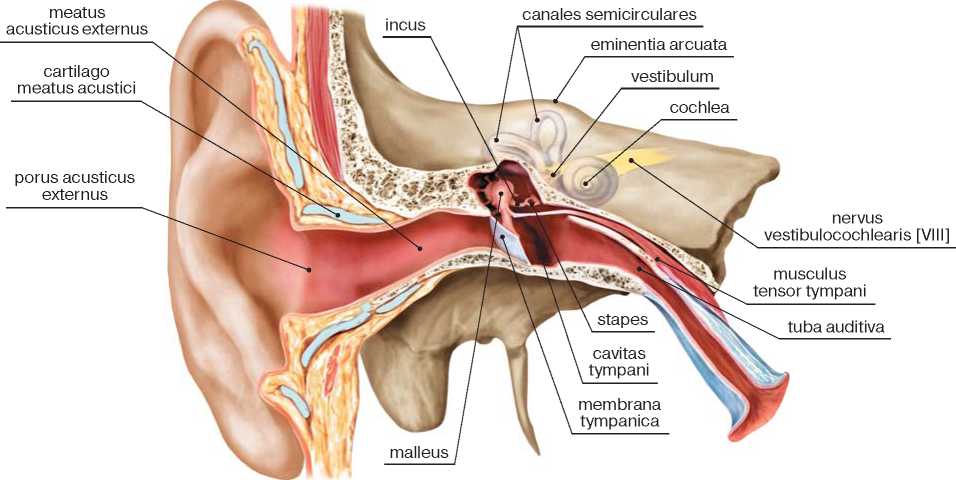

Анатомия и особенности фиссуры петротимпаника